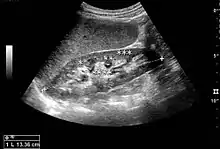

Figure 1. Normal adult kidney. Measurement of kidney length on the US image is illustrated by ‘+’ and a dashed line. *Column of Bertin; ** pyramid; *** cortex; **** sinus.[1]

The kidney is divided into parenchyma and renal sinus. The renal sinus is hyperechoic and is composed of calyces, the renal pelvis, fat and the major intrarenal vessels. In the normal kidney, the urinary collecting system in the renal sinus is not visible, but it creates a heteroechoic appearance with the interposed fat and vessels. The parenchyma is more hypoechoic and homogenous and is divided into the outermost cortex and the innermost and slightly less echogenic medullary pyramids. Between the pyramids are the cortical infoldings, called columns of Bertin (Figure 1). In the pediatric patient, it is easier to differentiate the hypoechoic medullar pyramids from the more echogenic peripheral zone of the cortex in the parenchyma rim, as well as the columns of Bertin (Figure 2).[1]

The length of the adult kidney is normally 10–12 cm, and the right kidney is often slightly longer than the left kidney. The adult kidney size is variable due to the correlation with body height and age; however, normograms for pediatric kidney size are available.[1]

Cortical thickness should be estimated from the base of the pyramid and is generally 7–10 mm. If the pyramids are difficult to differentiate, the parenchymal thickness can be measured instead and should be 15–20 mm (Figure 3). The echogenicity of the cortex decreases with age and is less echogenic than or equal to the liver and spleen at the same depth in individuals older than six months. In neonates and children up to six months of age, the cortex is more echogenic than the liver and spleen when compared at the same depth.[1]